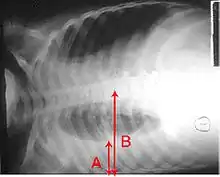

نوتروفیلها، باکتریها و مایع اطراف رگهای خونی آلوئولها را پر میکنند که منجر به ایجاد نقاط فشرده قابل مشاهده در تصویر اشعه ایکس قفسه سینه میشوند.[35]

تصاویر اشعه ایکس از سینه پهلو به سینه پهلو لختهای، سینه پهلو برونشی (همچنین با عنوان سینه پهلو بخشی شناخته میشود) و سینه پهلو بینابینی قابل طبقهبندی است.[41] سینه پهلو اکتسابی باکتریایی، بهطور معمول تجمع ریوی در یک لوب سگمنتال ریه را نشان میدهد که به آن سینه پهلو لختهای میگویند.[21] با این حال ممکن است یافتهها متفاوت باشند و الگوهای دیگری در انواع دیگر سینه پهلو شایع است.[21] سینه پهلو آسپیراسیون ممکن است با تیرگی دوطرفه و عمدتاً در پایین ریهها و در سمت راست وجود داشته باشد.[21] تصاویر رادیوگرافی سینه پهلو ویروسی ممکن است طبیعی به نظر برسد، بیش از حد متورم باشد، مناطق لکهدار در هر دو طرف مشاهده شود، یا شبیه سینه پهلو باکتریایی، تجمع لختهای را نشان دهد.[21] ممکن است نتایج رادیولوژی در مراحل اولیه بیماری مشاهده نشود، بهویژه در صورتی آب بدن از دست رفته باشد؛ یا ممکن است تفسیر آن در کسانی که چاق هستند یا سابقه بیماری ریوی دارند، دشوار باشد.[12] سیتی اسکن میتواند اطلاعات بیشتری را در موارد نامشخص در اختیار قرار دهد.[21]